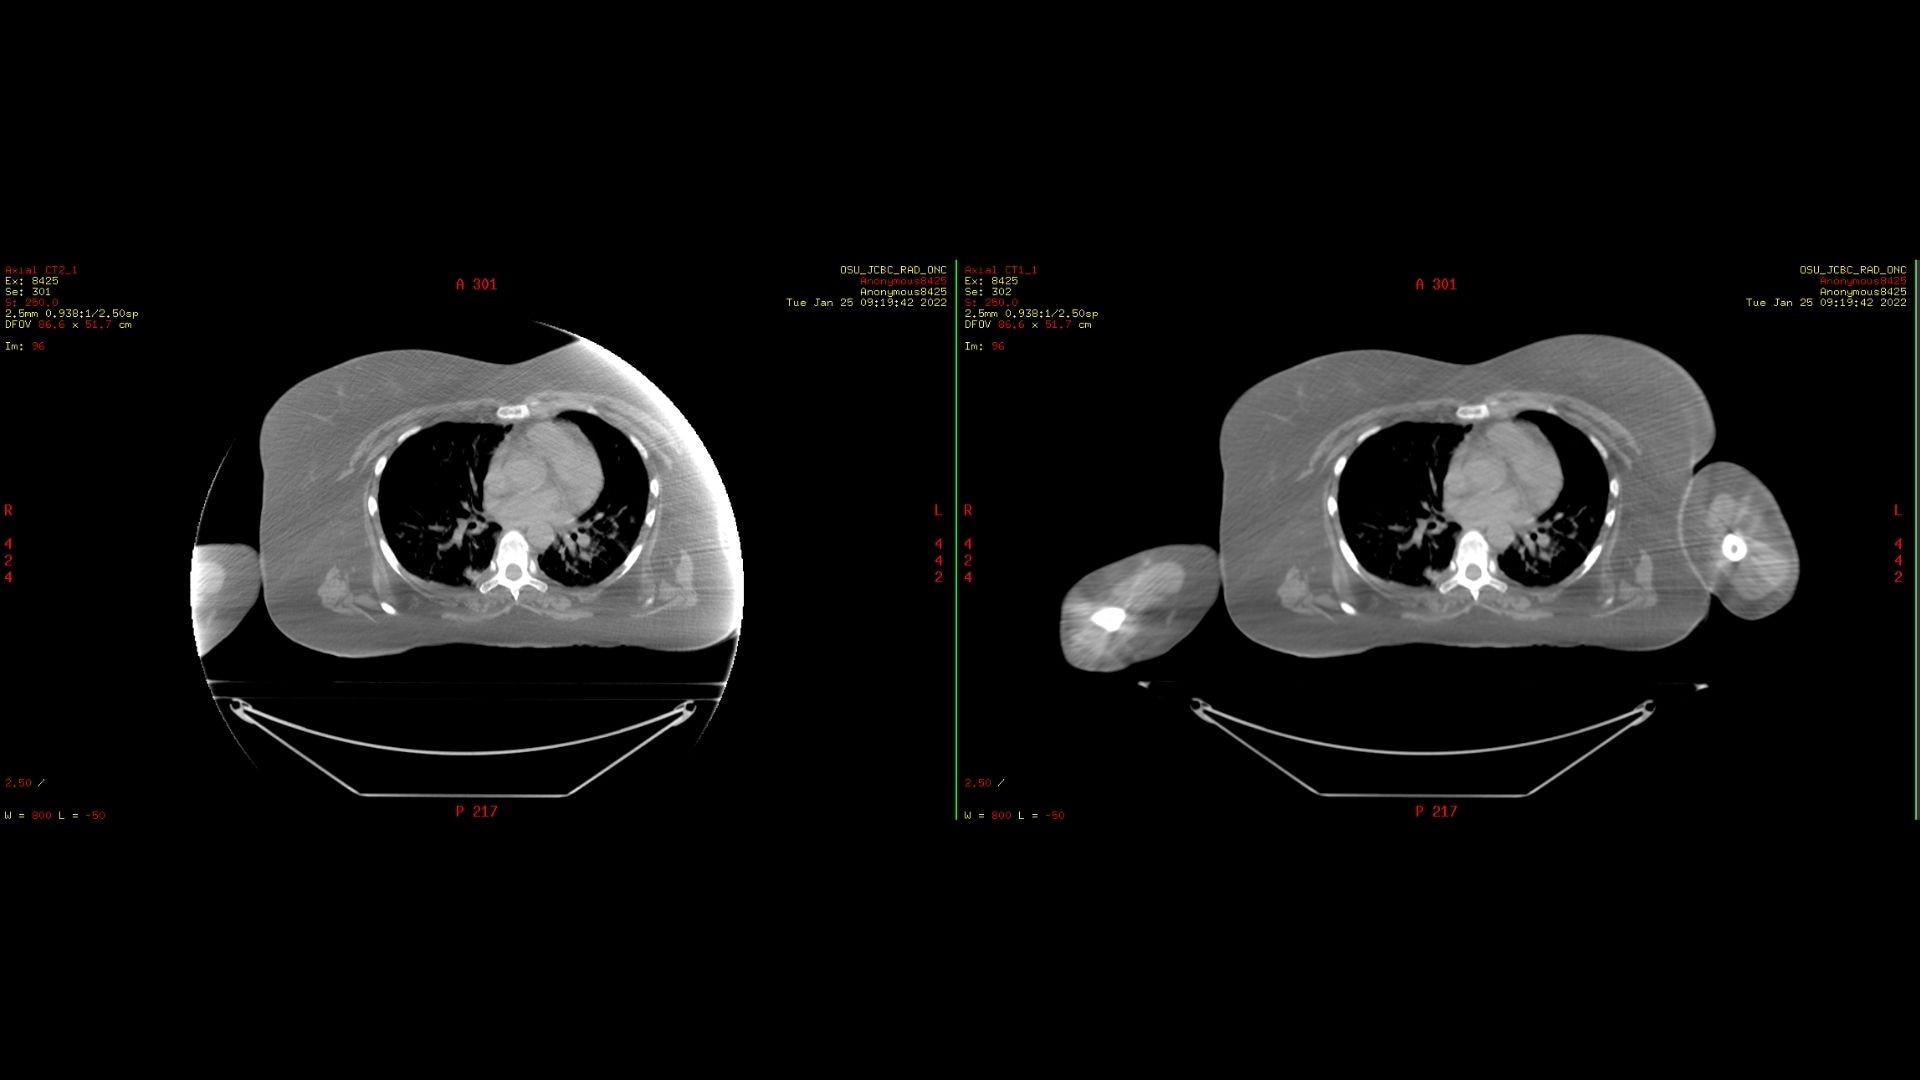

Грудная клетка в положении лежа на спине с MaxFOV-2 и без него